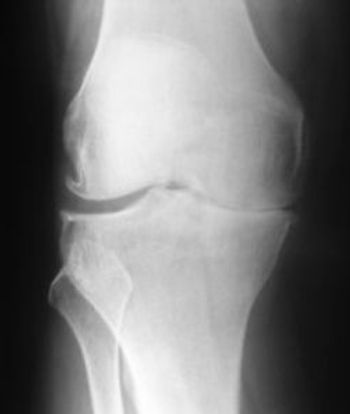

Arthritic pain is caused due to a loss of cartilage in the joints where the pain is caused. This in turn causes a narrowing of the gap between the ends of the bones. This can be seen on the picture to the left, as the gap between the different bones is only visible on one side of the bone. This causes a constant rubbing between the bones when they are moved which causes painful sensations in the individual.